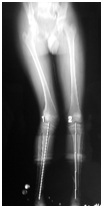

Figure 4 Case 9 (A: preoperative scannog ram, B: scannogram after full correction).